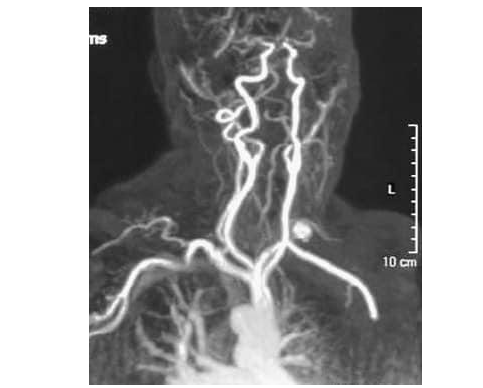

السوسنة - تمكن فريق الأشعة التداخلية في مستشفيات البشير من إنقاذ حياة مريضة عشرينية كانت تعاني من كيس دموي نازف في أحد أفرع الشريان تحت الترقوة الأيسر.

وقال الأستاذ الدكتور في الاشعة التداخلية موفق الحيص إنه تم وضع مجموعة من الحلقات في الكيس الدموي أدت إلى إغلاق الكيس الدموي بالكامل.

وأضاف الحيص أنه تم التأكد من إغلاق الشريان بالكامل ومتابعة المريضة من خلال إجراء قسطرة بعد ٦ شهور من وضع الحلقات ومن خلال التصوير التلفزيوني الملون و الفحص السريري الذي يبين ان جميع شرايين الطرف السفلي محسوسة مسموعة.

ولفت الدكتور الحيص أن هذه الحالة من الحالات النادرة في العالم.